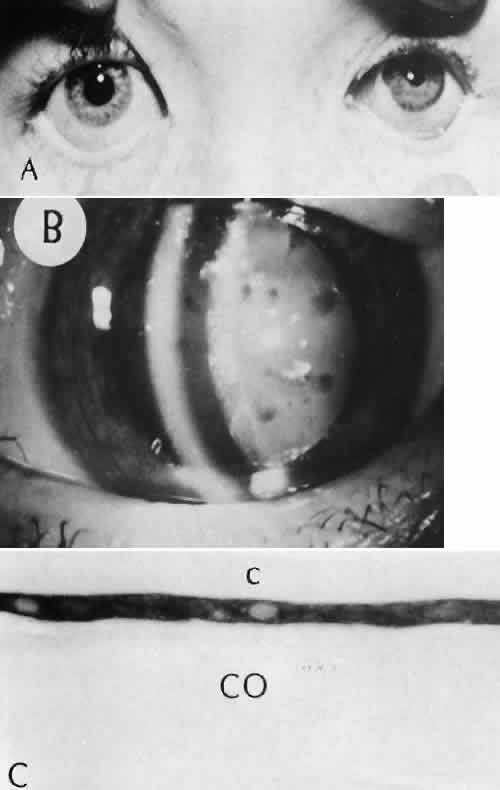

Cyclocryotherapy, cyclodiathermy (Fig. 20), and therapeutic ultrasonography apply energy directly to the pars plicata and cause lysis of the ciliary muscle and occlusion of the vascular supply, leading to extensive necrosis and scarring. Pressure lowering is accomplished by a reduction of aqueous production. Heat applied to the sclera may cause necrosis and localized scleral thinning. Cold applied to the sclera, unless extreme, does not cause any clinical or histologic changes.

Fig. 20. Cyclodiathermy treatment of the ciliary body to control glaucoma. A. Gross photograph illustrates extensive areas of depigmentation mainly in the region of the pars plana (arrows) rather than the pars plicata. B. Light micrograph of the region of the pars plana illustrates an extensive area of tissue degeneration of the pars plana (between arrows) in the late postoperative course. C. Light micrograph of the destructive effects of cyclocryotherapy also in the region of the pars plana and pars plicata. The ciliary epithelium in the early postoperative period is necrotic and cystic. (Hematoxin-eosin stain; A, × 8; B, × 16.)